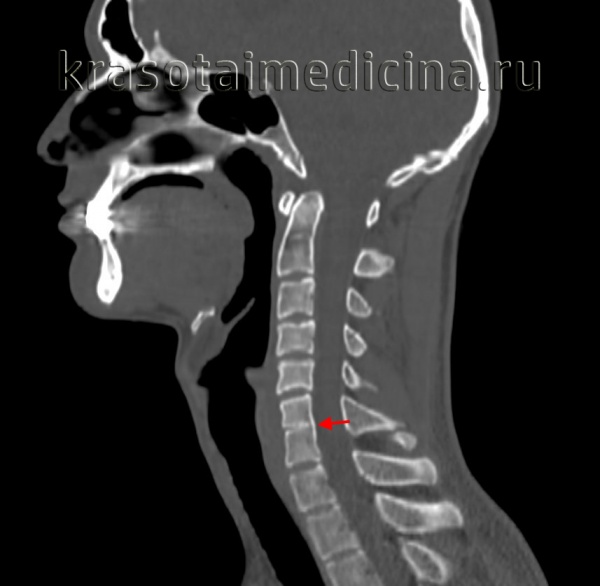

Умственная отсталость у детей с синдромными краниосиностозами в зависимости от возраста на момент операции. Распространенность непрогрессирующей вентрикуломегалии и гидроцефалии при синдромных краниосиностозах. Виды операций при синдромных фациокраниосиностозах. Три поколения пациентов с синдромом Крузона. Слева: МРТ (сагиттальная проекция) мозга у ребенка с синдромом Крузона.

Обратите внимание на акроцефальную форму черепа и сопутствующие деформации церебральных структур,

расширение желудочков и каудальное смещение миндалин мозжечка (мальформация Киари I типа).

Справа: ангиография в венозной фазе. Отметьте призанки нарушения венозного оттока, сочетающегося с коллатеральными дренажами (стрелка). Слева: интраоперационная КТ головы у ребенка с синдромом Крузона.